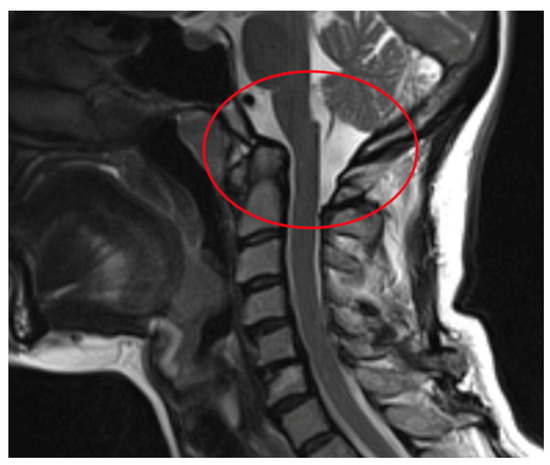

| AAS (atlantoaxial subluxation) | Weakening or rupture of ligaments and subchondral bone erosion in the atlantoaxial C1–C2 joints. |

| SAS (subaxial subluxation) | Subluxation in the joints C2–C7 due to destruction of the joint surface and the ligaments between the processes spinosis. |

| CS (cranial settling) | Vertical translocation of dens C0–C2 into the foramen magnum. |